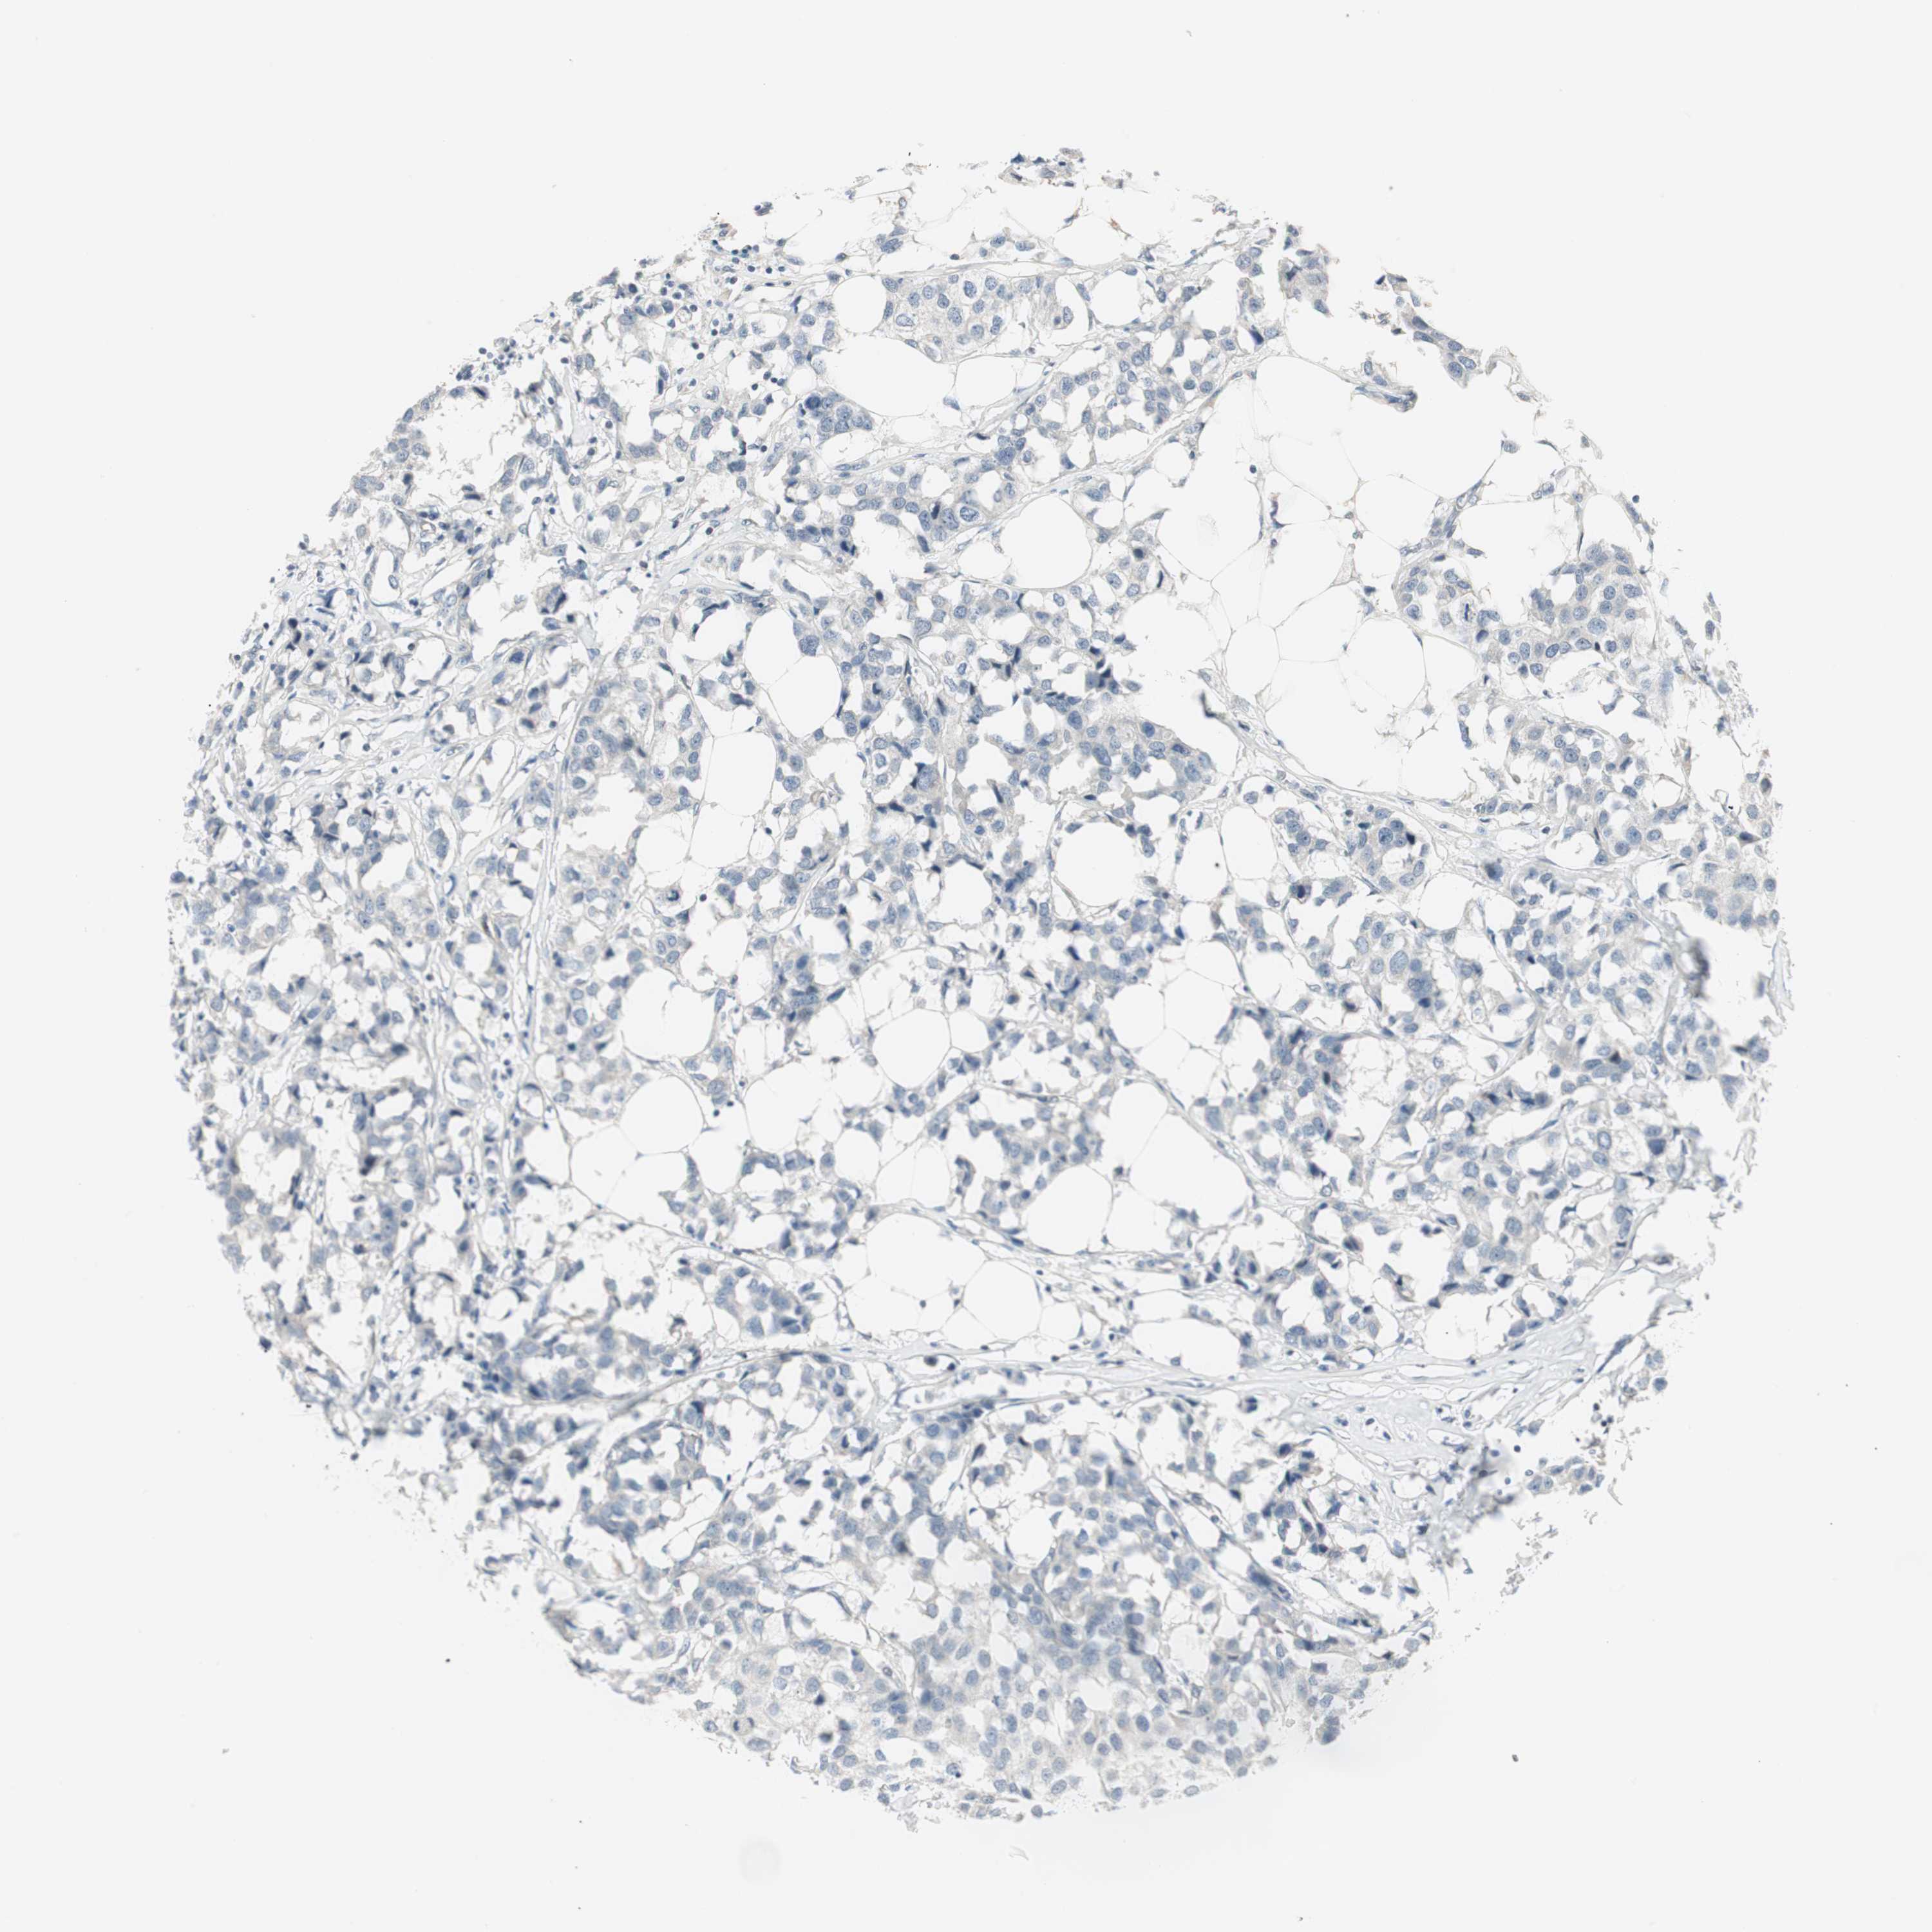

CANCER BREAST CANCER Show tissue menu

BRCA TCGA BRCA VALIDATION PROTEIN EXPRESSION

ITGB4 is not prognostic in Breast Invasive Carcinoma (TCGA)